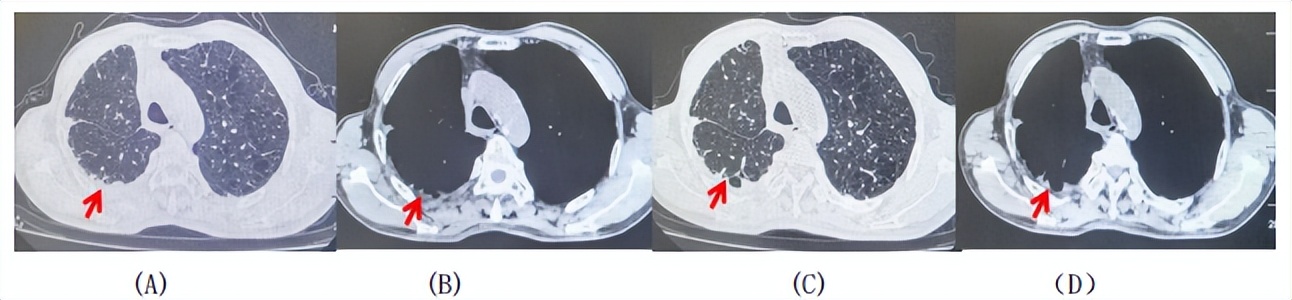

2024.11.19患者出现右侧胸痛,复查胸部CT检查示右侧胸膜肿物,大小约31mmX24mm,右侧4、5肋骨骨质破坏,考虑转移(如图2)。建议患者穿刺活检取病理明确诊断,患者拒绝,经MDT会诊后结合影像学表现及病史考虑为胸膜转移,肋骨转移,分期为rT0N0M1a IVA期,DFS仅仅17个月。2024.12.05起行信迪利单抗联合培美曲塞+卡铂方案治疗4周期,复查胸CT评效PR(如图3)。之后给予信迪利单抗+培美曲塞维持治疗6周期,期间复查CT评效PR(如图3)。目前信迪利单抗+培美曲塞维持治疗中,截止至目前PFS约为8个月,治疗期间未出现明显毒副反应。

图1:患者手术前(2023.06)胸部CT肺窗及纵隔窗

图3:患者免疫联合化疗治疗后胸部CT,(A、B)图展示信迪利单抗联合培美曲塞+卡铂治疗

4周期(2025.02)疗效,(C、D)图展示信迪利单抗+培美曲塞维持治疗6周期(2025.07)疗效